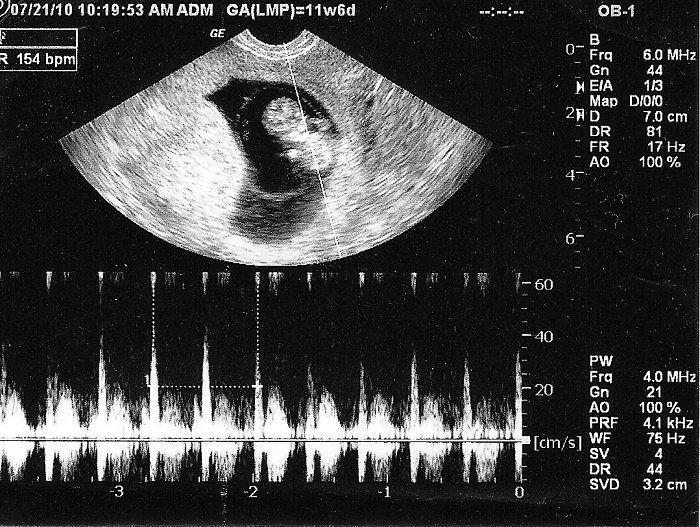

3. Đọc kết quả siêu âm thai 6 tuần

Siêu âm thai 6 tuần tuổi chưa ghi nhận được hết tất cả các chỉ số thai nhi cần thiết vì thai còn quá nhỏ. Tuy nhiên, một vài chỉ số của thai 6 tuần được ghi nhận qua siêu âm phần nào giúp đánh giá mức độ phát triển của thai nhi, các chỉ số đó bao gồm:

- GSD (Gestational Sac Diameter): là kích thước túi ối. Chỉ số GSD có thể đo được những tuần đầu tiên thai kỳ, thời điểm các cơ quan trong cơ thể vẫn chưa hình thành. Khi thai 6 tuần tuổi, chỉ số GSD khoảng 14-25mm

- CRL (Crown rump length) là chiều dài đầu mông. Trong kết quả siêu âm thai 6 tuần, chỉ số CRL bình thường khoảng 4-7mm.

- Tim thai: Thông thường, siêu âm ghi nhận được tim thai ở tuần thứ 7 và rõ ràng nhất từ tuần 12 trở đi. Khi thai 6 tuần tuổi, tim thai đã sắp sửa thành hình nên ở những thai nhi phát triển tốt và khỏe mạnh thì đôi khi siêu âm thai 6 tuần tuổi đã có thể ghi nhận được nhịp tim em bé.